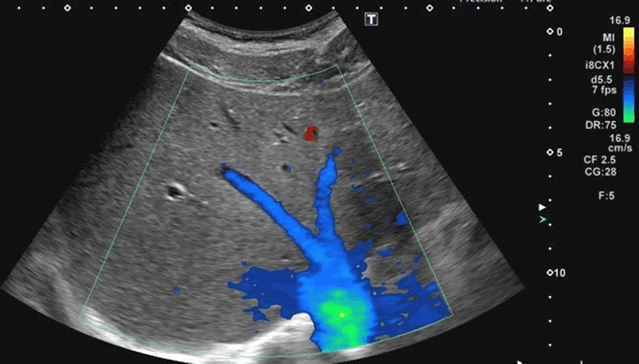

ドプラ法の原理から適切な設定法、アーチファクトの対処まで解説しています。非侵襲的に血流情報を診断に活かす手法をマスターしましょう。